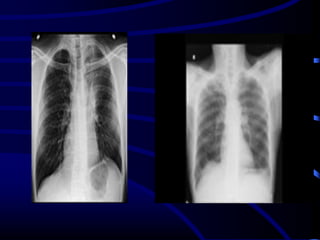

Case 3

A 54-year-old female nonsmoker complained of

shortness of breath on exertion and a dry

cough.

What is the MOST

LIKELY diagnosis?

A. RB_ILD.

B. Non specific interstitial

fibrosis

C. IPF.

D. CVD

E. Subacute hypersensitivity

pneumonitis.